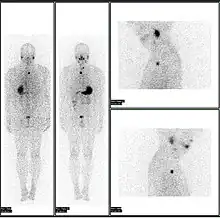

Normal whole body PET/CT scan with FDG-18. The whole body PET/CT scan is commonly used in the detection, staging and follow-up of various cancers.

Abnormal whole body PET/CT scan with multiple metastases from a cancer. The whole body PET/CT scan has become an important tool in the evaluation of cancer.